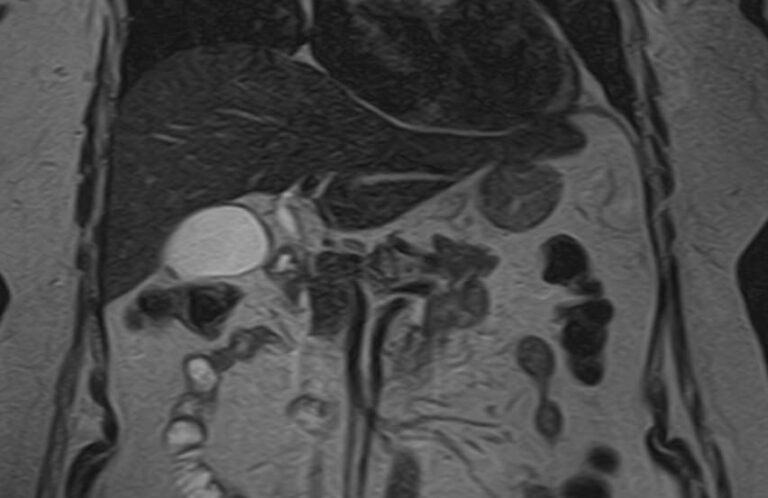

Исследование желчных протоков и пузыря методом МРТ помогает объективно оценить состояние билиарного тракта и выявить патологические изменения на ранних этапах развития. Исследование проводят при подозрении на инфекционный, воспалительный или опухолевый процесс, а также для исключения конкрементов. МР-диагностика позволяет определить локализацию и характер патологических изменений и установить окончательный диагноз.